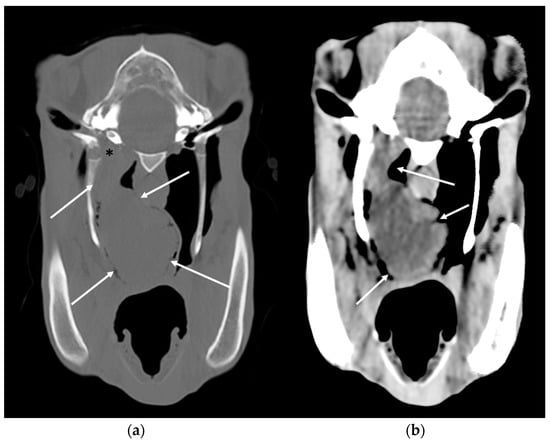

2.3. Cross-Sectional Imaging

3.4. Temporohyoid Osteoarthropathy

3.5. Masses Involving the Guttural Pouches